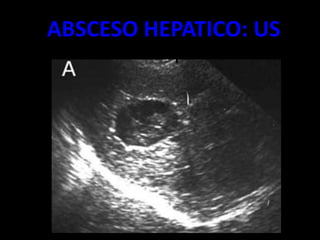

ABSCESO HEPATICO

• LESIÓN POR LO GENERAL BIEN DELIMITADA

• DENSIDAD SUELE SER ALGO SUPERIOR A LA DEL

AGUA (20-30 UH).

• TRAS LA INYECCIÓN DE CONTRASTE INTRAVENOSO

MUESTRA UNA INTENSA CAPTACIÓN ANULAR QUE ES

MUY CARACTERÍSTICA AUNQUE NO

PATOGNOMÓNICA

• UN BAJO PORCENTAJE DE ABSCESOS HEPÁTICOS

CONTIENEN GAS EN SU INTERIOR.

• EN TC

– SENSIBLE 90 %

– MASAS REDONDEADAS

– BAJA ATENUACIÒN C/S CONTRASTE

– ATENUACIÒN ENTRE 0 Y 45 UH.

– COALECER.

– NIVELES HIDROAEREOS. (INTESTINO/ABSCESO)

ABSCESO HEPATICO: US